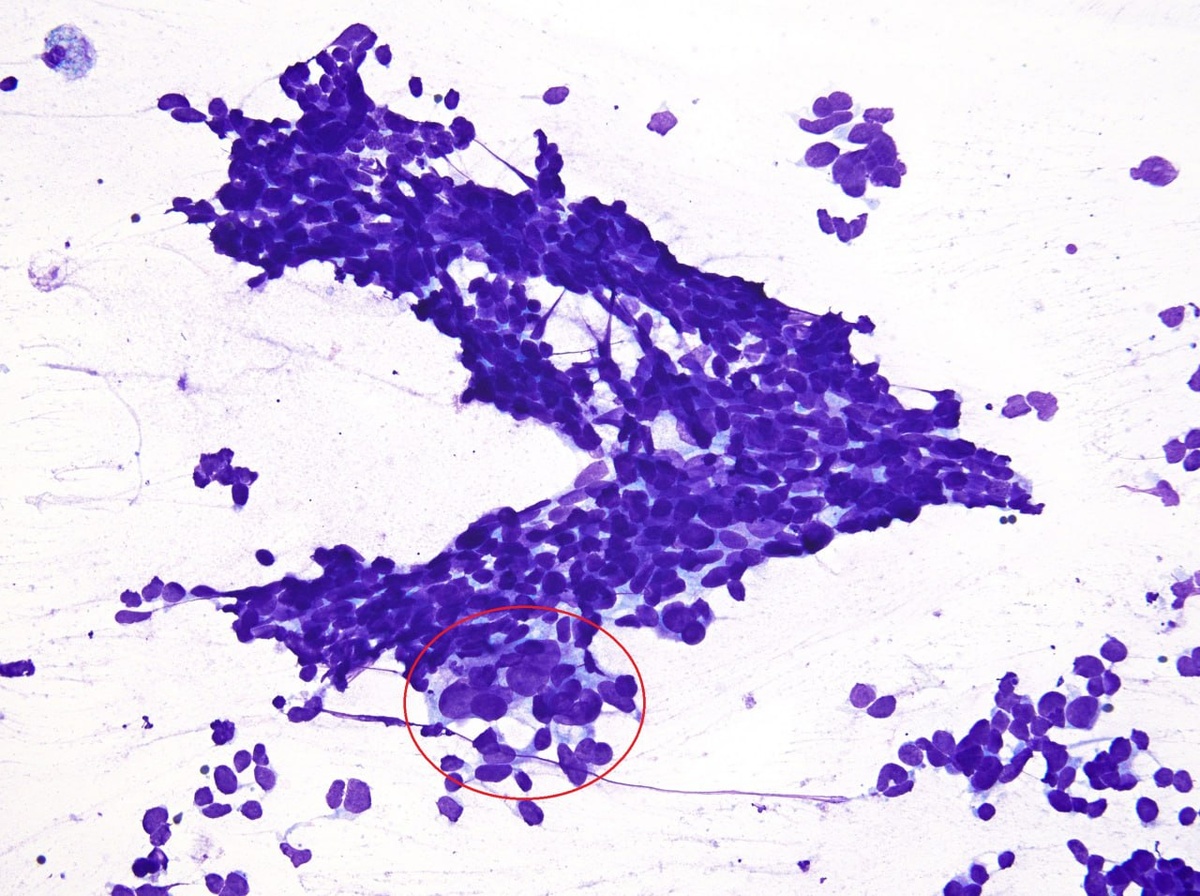

Исключительно редкий случай пункционной биопсии щитовидной железы у пациента с ALK-положительной аденокарциномой легкого в анамнезе.

При ранее проведенной пункционной биопсии надпочечника была выявлена смешанная мелкоклеточная карцинома с аденокарциномой, обе компоненты которой экспрессировали TTF-1.

Биопсия щитовидной железы преимущественно представлена мелкоклеточным раком с минимальной примесью аденокарциномы (обведено красным), соответствующей известному первичному очагу в лёгких.